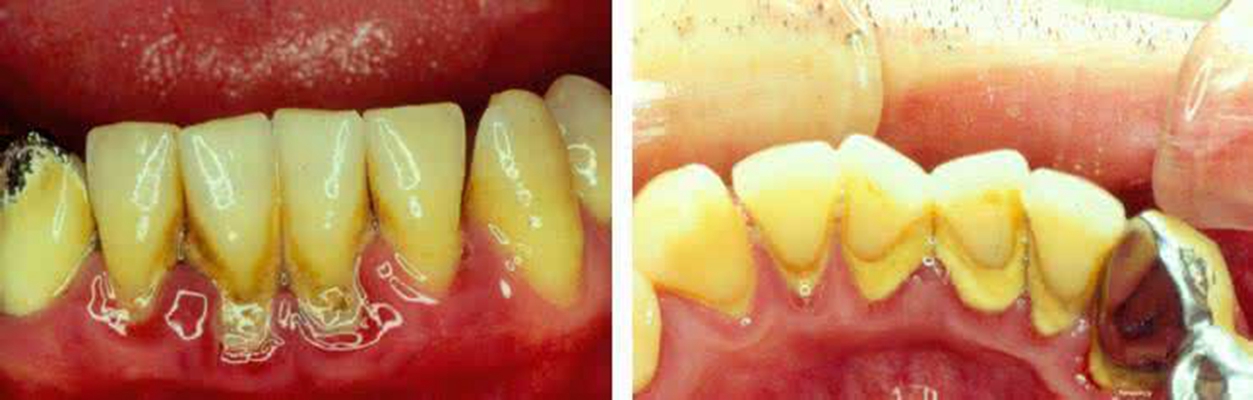

牙周袋 (7)

牙周袋 (8)